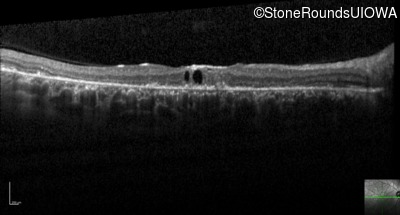

Optical Coherence Tomography - Right - 20/200 -2

Exemplar / OCT Stack